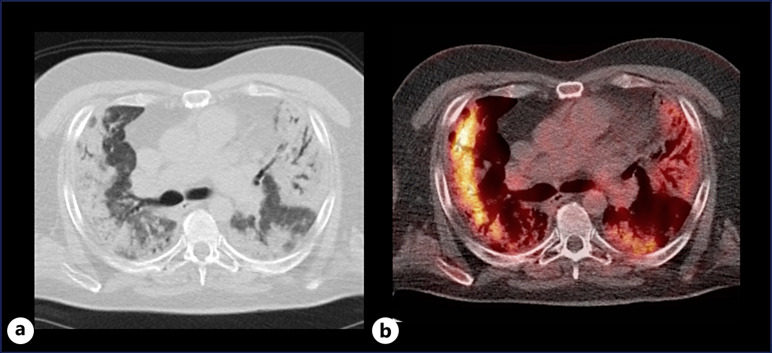

Case presentation: A 50-year-old patient underwent double lung transplantation (LTx) in July 2018 for progressive fibrosing interstitial lung disease (ILD). IMA was unexpectedly found in the explant lungs. Pre-transplant PET-CT scans suggested inflammatory ILD without malignancy. Endobronchial ultrasound-guided transbronchial fine needle aspiration of the enlarged mediastinal lymph nodes demonstrated no evidence of malignancy. Post-transplant pathology confirmed stage IVA IMA with a KRAS G12D mutation. After 3 years, recurrent IMA was detected. The asymptomatic patient remains under close surveillance with stable lung function, and tailored treatment will be considered if progression occurs.